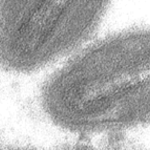

Mpox: How Is Mpox Virus Transmitted?

The monkeypox virus or MPOXV is a double-stranded DNA virus that belongs to the Orthopoxvirus genus in the Poxviridae family. It is a disease-causing and […]

Treatment For Mpox Disease And Vaccines Against Mpox Virus

Public attention toward the monkeypox disease or mpox and the monkeypox virus has emerged following a series of outbreaks outside of Africa that began in […]